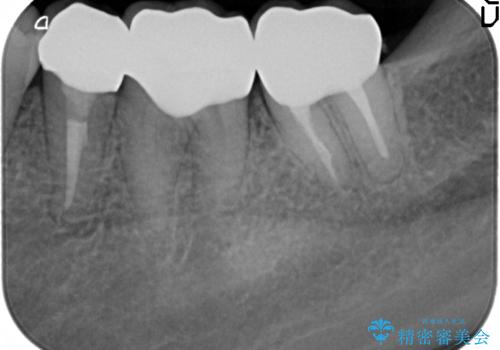

- 45万円(仮歯・ファイバーコア・ジルコニアクラウン×3 歯周外科手術)費用は治療当時の料金となります

セラミック治療の注意事項(リスク・副作用など)

- 天然歯を削ります

- 硬い素材は天然歯を傷つけてしまう場合があります

- かみ合わせや歯ぎしりが強すぎる方はセラミックが割れてしまう可能性があります